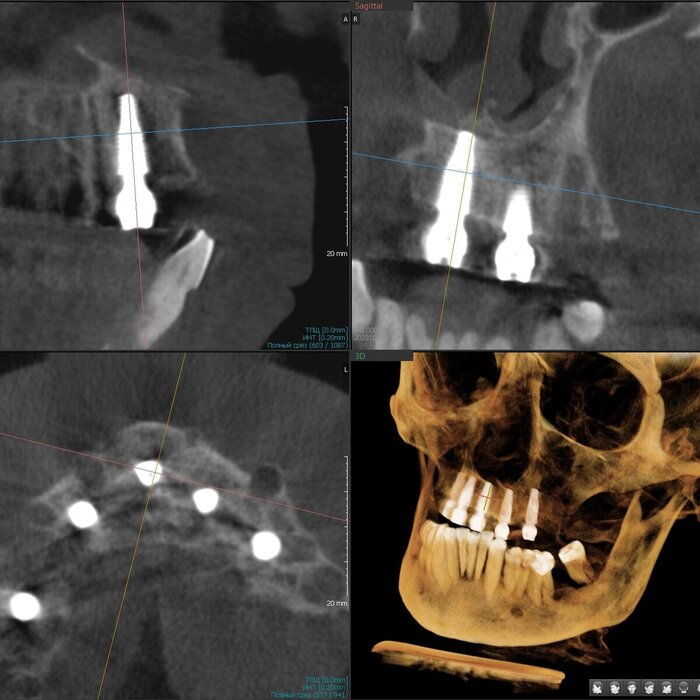

Делаем КЛКТ.

3Д визуализация костей черепа.

Так, мне уже всё понятно - хронический генерализованный пародонтит тяжёлой степени тяжести.

Посмотрим срезы.

Пародонтит.

Зубы цепляются за кость верхушками корней.

Пародонтит.

Куда ни глянь - одна картина.

Пародонтит.

Деструкция кости капитальная.

Пародонтит + периодонтит.

Хуже пародонтита может быть только присоединившийся к нему периодонтит (воспалительный процесс на верхушке корня/корней, в народе "киста") - вот уж где разрушение кости глобальным образом проявляется.

Периодонтит.

Кортикальные пластики утеряны, жаль.